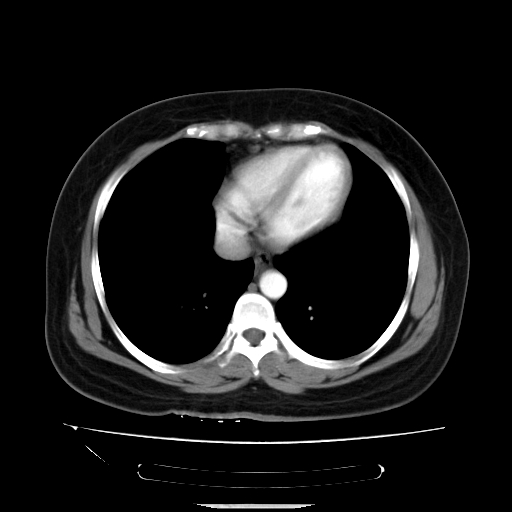

标题: CT14225:女性46岁。当地B超示肝内占位,来我院作CT检查。请 [打印本页]

标题: CT14225:女性46岁。当地B超示肝内占位,来我院作CT检查。请

速升速降,支持肝癌.脾体积增大,形态欠规整,请询问病史是否做过脾动脉栓塞.

速升速降,支持肝癌可能。

快进快出,符合肝癌表现-----------

肝内结节强化特点符合原发性肝癌表现,脾脏改变考虑为增大及先天发育所致。

动脉期病原灶明显强化高于肝密度且中央有无强化区,静脉期强化程度下降明显,延迟低于肝密度,考虑肝腺瘤可能性大,

肝内结节强化特点:快进快出符合原发性肝癌表现

此患者虽然符合快进的特点,却不符合快出的特点,因为门脉期几乎是等密度,不符合肝癌的增强表现,所以我考虑肝局灶性结节增生可能性大